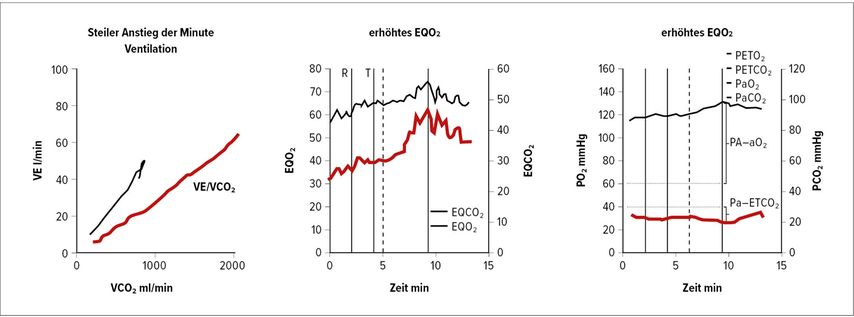

Spirometrie (Abb. 1) und DLCO (Diffusionskapazität für Kohlenmonoxid) helfen zur Erkennung von COPD, interstitiellen Lungenerkrankungen oder Hypoventilationssyndromen. Hochauflösende CT-Thoraxuntersuchungen sind unerlässlich zur Erkennung von parenchymatösen Lungenerkrankungen, Emphysem und Fibrose. Ventilations-/Perfusions-Scan (V/Q-Scan) ist empfohlen bei allen Patienten mit Verdacht auf PH zum Screening auf CTEPH, da eine hohe Sensitivität für Perfusionsdefekte besteht (Abb. 2). CT-Lungenangiografie (CTPA) liefert anatomische Details bei Verdacht auf CTEPH oder akute Lungenembolie. Die Schwäche der CTPA ist ihre schlechte Auflösung in distalen kleinen Gefäßen.

Abb. 1: Von links nach rechts Panels 4, 6 und 9 der Wassermannplots bei Lungengefäßerkrankung. In der Abbildung zeigen rote Kurvenlinien die Lungengefäßerkrankung an, die schwarzen Kurven stammen von normalen Kontrollen. EQO2 steht für ventilatorisches Sauerstoff-Äquivalent berechnet als Atemminutenvolumen/Sauerstoffaufnahme (VO₂), PETCO₂ steht für endtidales CO₂

5. Kardiopulmonale Belastungsuntersuchung (CPET)

CPET kann zwischen kardialen und pulmonalen Einschränkungen unterscheiden und deckt frühe pulmonale Gefäßerkrankungen auf. CPET erlaubt die Früherkennung von belastungsinduzierter PH bei Patienten mit hohem Krankheitsrisiko, z.B. homozygote Träger von BMPR2-Mutationen, ist aber wenig spezifisch.